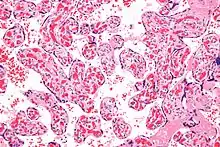

Micrograph of a chorangiosis. H&E stain.

Chorangiosis is a placental pathology characterized by an abundance of blood vessels within the chorionic villi.

It is diagnosed by a microscopic examination of the placenta.

Commonly used criteria from Altshuler[2][3] are: "a minimum of 10 villi, each with 10 or more vascular channels, in 10 or more areas of 3 or more random, non-infarcted placental areas when using a ×10 ocular." The Altshuler criteria are not theoretically rigorous, as they do not define the area. Normal villi have up to five vascular channels.[3]